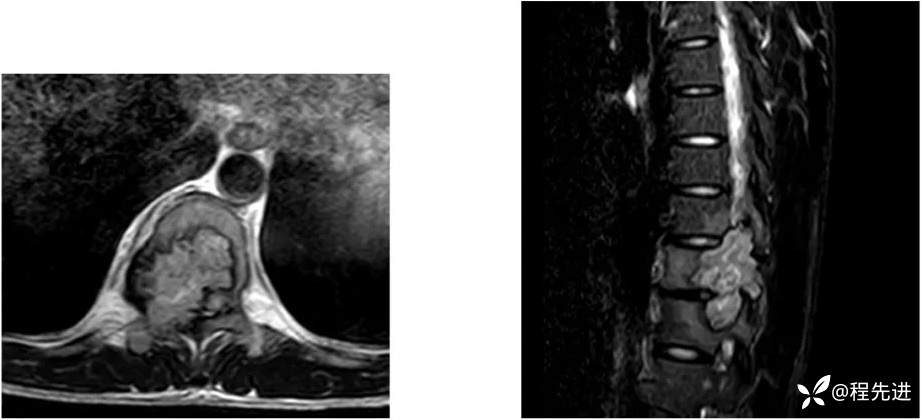

【患者信息】:男,29岁

【现病史及既往史】:双下肢麻木无力5月余,有踩棉感

【检查】